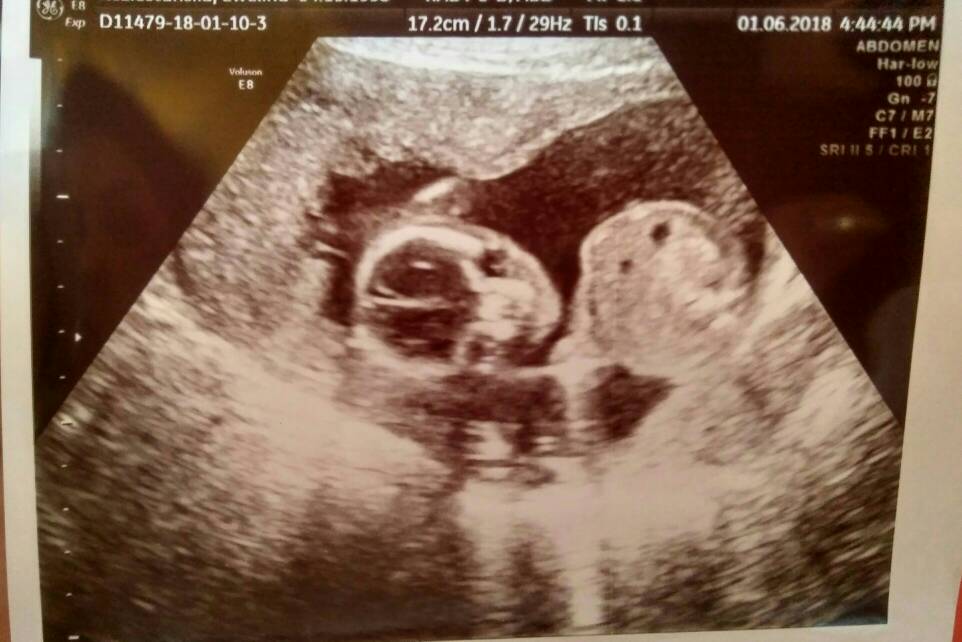

Dziewczyny a ja właśnie po wizycie :)

Maluszek ładnie rośnie i wszystko jest prawidłowo. Będzie Adaś ;)

Dostałam zdjęcie główki z oddali, załączam :)Zobacz załącznik 862767